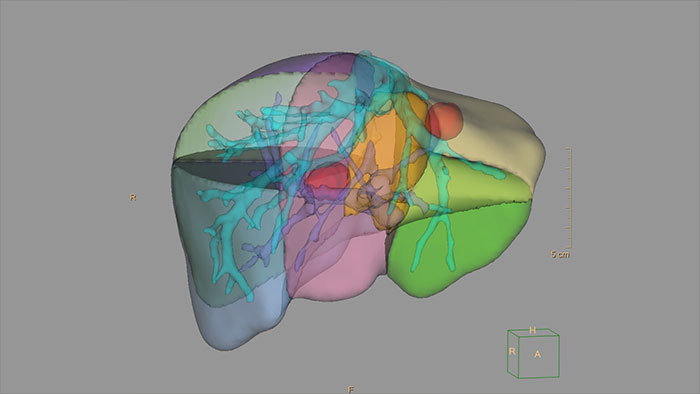

Advanced Liver segmentation

Automatically identifies, segments and quantifies the liver from the portal venous phase of a tri-phase liver scan and classifies the hepatic and portal veins.